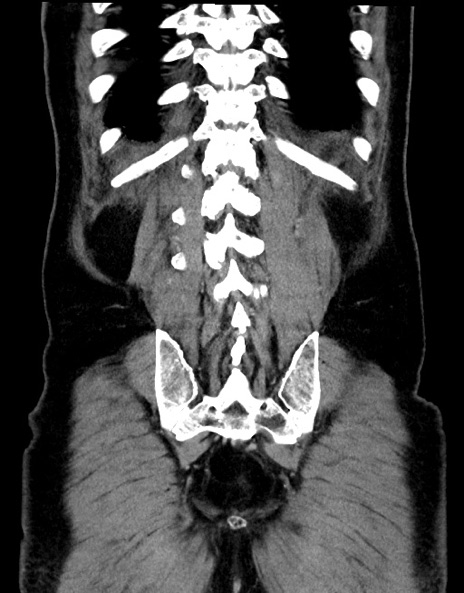

症例15(冠状断像)

【症例】70歳代男性

【主訴】腹痛

【現病歴】今朝から腹痛あり。全体的に痛い。特に左上の方。排ガスが今日はない。冷や汗が出る。

【既往歴】直腸癌術後

【身体所見】左側腹部〜上腹部に圧痛あり。腹膜刺激症状明らかなではない。軽度反跳痛。左下腹部に術後瘢痕あり。

【データ】WBC 7700、CRP 0.02

横断像